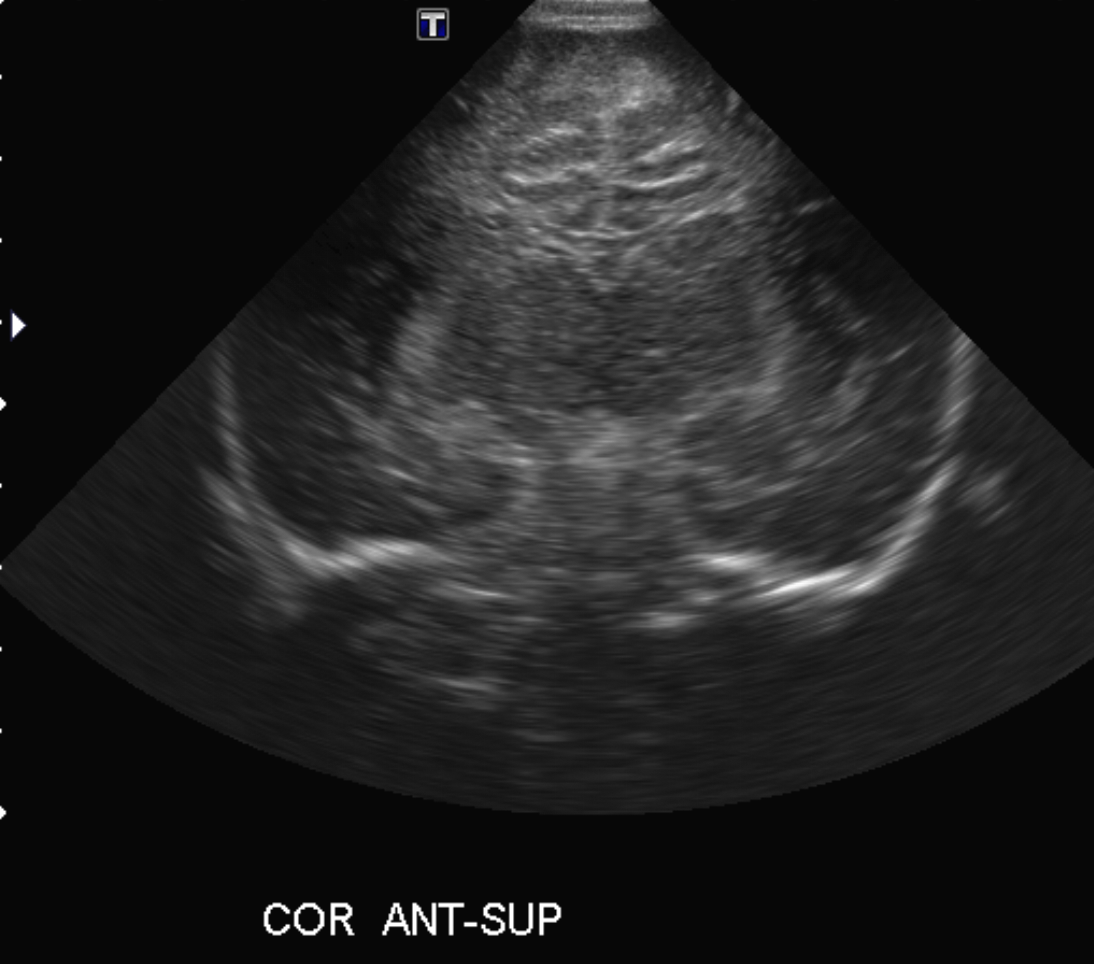

Info Images Findings Impression Reco/Acuity Case Images View Images / Launch Visage Case Notes History Full term infant. We are asked to evaluate posterior fossa cyst. Exam Gray scale and Doppler Ultrasonographic examination of the head. Prior Study N/A Dicom View Reference Material

Section 1 Submit Findings Case149 Findings Brain The brain is immature. Yes No There is under-sulcation and open sylvian fissures. Yes No There is/are multiple hypoechoic areas in the periventricular white matter. Yes No There is/are multiple hyperechoic areas in the periventricular white matter. Yes No There is diffuse cerebral edema with diffusely increased echogenicity of the brain parenchyma and loss of grey white matter differentiation. Yes No The thalami/basal ganglia are hypoechoic. Yes No There is periventricular calcification. Yes No There is intra-parenchymal calcification. Yes No CSF spaces/ventricular system There is a prominence of the extra axial fluid spaces. Yes No There are debris/septations in the extra axial fluid spaces. Yes No There are debris/septations in the ventricles. Yes No There is a subdural collection on the right/left side. Yes No There is prominence of the ventricular system. Yes No There is an asymmetry of the ventricular system. Yes No There is a cavum septum pellucidum. Yes No There is a midline shift towards right/left. Yes No The choroid plexus is bulky/lobulated. Yes No There is a choroid plexus cyst measuring… Yes No There are debris/clots in the occipital horn. Yes No There is a posterior fossa cyst measuring… Yes No The tentorium is elevated/depressed. Yes No The lateral ventricle/s are dilated. Yes No The third ventricle is dilated. Yes No The 4th ventricle is dilated. Yes No There are pseudo cysts. Yes No Germinal matrix hemorrhage (Only in the premature infants): Please do not answer if the patient is a full term. There is a germinal matrix hemorrhage, consistent with a grade I hemorrhage. Yes No There is an intraventricular extension consistent with a grade II hemorrhage. Yes No There is an intraventricular extension with the dilatation of ventricles, consistent with a grade III hemorrhage. Yes No There is an intra-parenchymal extension, consistent with grade IV hemorrhage. Yes No On color Doppler examination, the Resistive index in the anterior cerebral artery is… There is a loss of the diastolic flow on the Doppler exam. Yes No There is altered vascularity on Doppler imaging. Yes No There is an AVM in the region of… Yes No